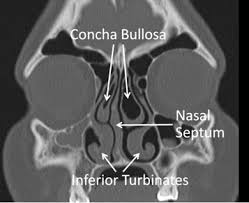

Fonksiyonel rinoplasti, septum deviasyonu, konka hipertrofisi, konka bülloza ya da burun içinde yer alan diğer anatomik anormalliklerin giderilmesini kapsar. Bu tür sorunlar, dışarıdan fark edilmediği için çoğu zaman estetik kaygılarla gelen hastalarda gözden kaçabilir. Ancak bu noktada devreye giren doğru uzman değerlendirmesi, hem estetik beklentileri hem de fonksiyonel ihtiyaçları aynı anda karşılayan bir çözüm sunar.